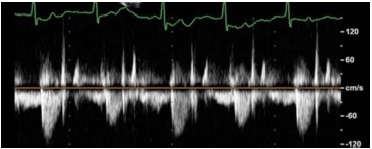

Em relação à figura a seguir, identifique a condição patológica evidenciada no fluxo aórtico na via de saída do VE.